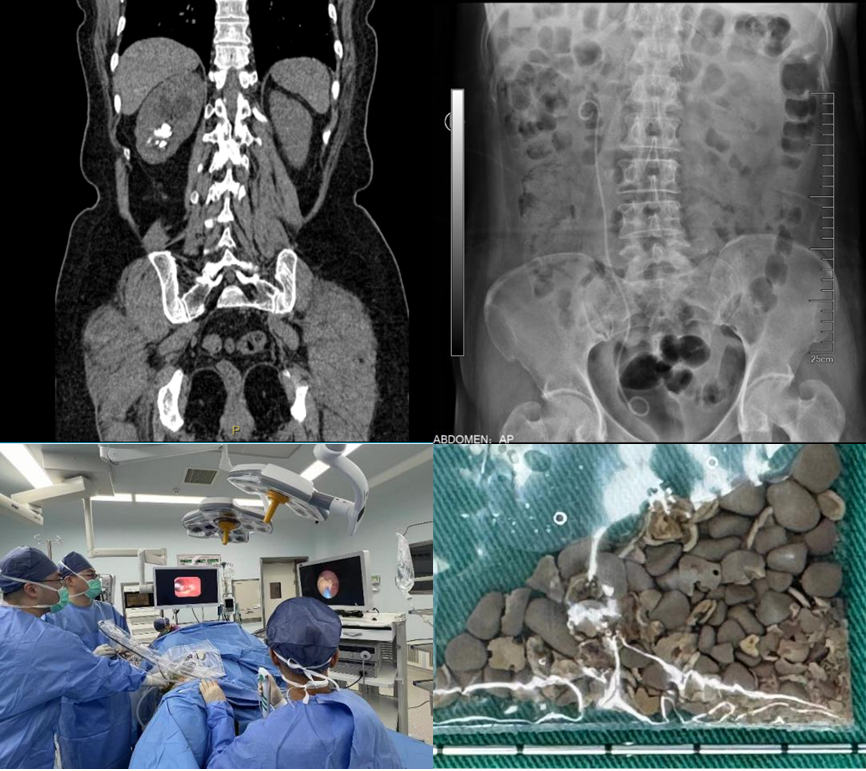

患者双肾结石多年,既往有多次结石手术病史,因为右腰部疼痛入院,检查后发现患者双肾多发结石。左侧为完全“鹿角型”结石,结石充满了整个肾脏,右侧输尿管也有多颗结石。浦金贤主任指出,患者双肾结石负荷大,左侧尤甚,且合并右侧输尿管结石,手术难度大,风险高,需优先保护肾脏功能,解除梗阻,尽可能彻底清除结石,减少术后再发概率。

经过科室讨论,周守军主任决定以分期手术的方式,借助智能控压清石系统,通过输尿管软镜处理右侧肾及输尿管结石。而对于左侧的无积水完全“鹿角型”结石,周主任在手术过程中一期采用标准通道经皮肾镜,结合第五代EMS超声弹道碎石系统清除结石主体,二期通过输尿管软镜配合末端可弯曲负压吸引鞘清除残余结石。术后患者恢复迅速,解决了困扰多年的结石问题。